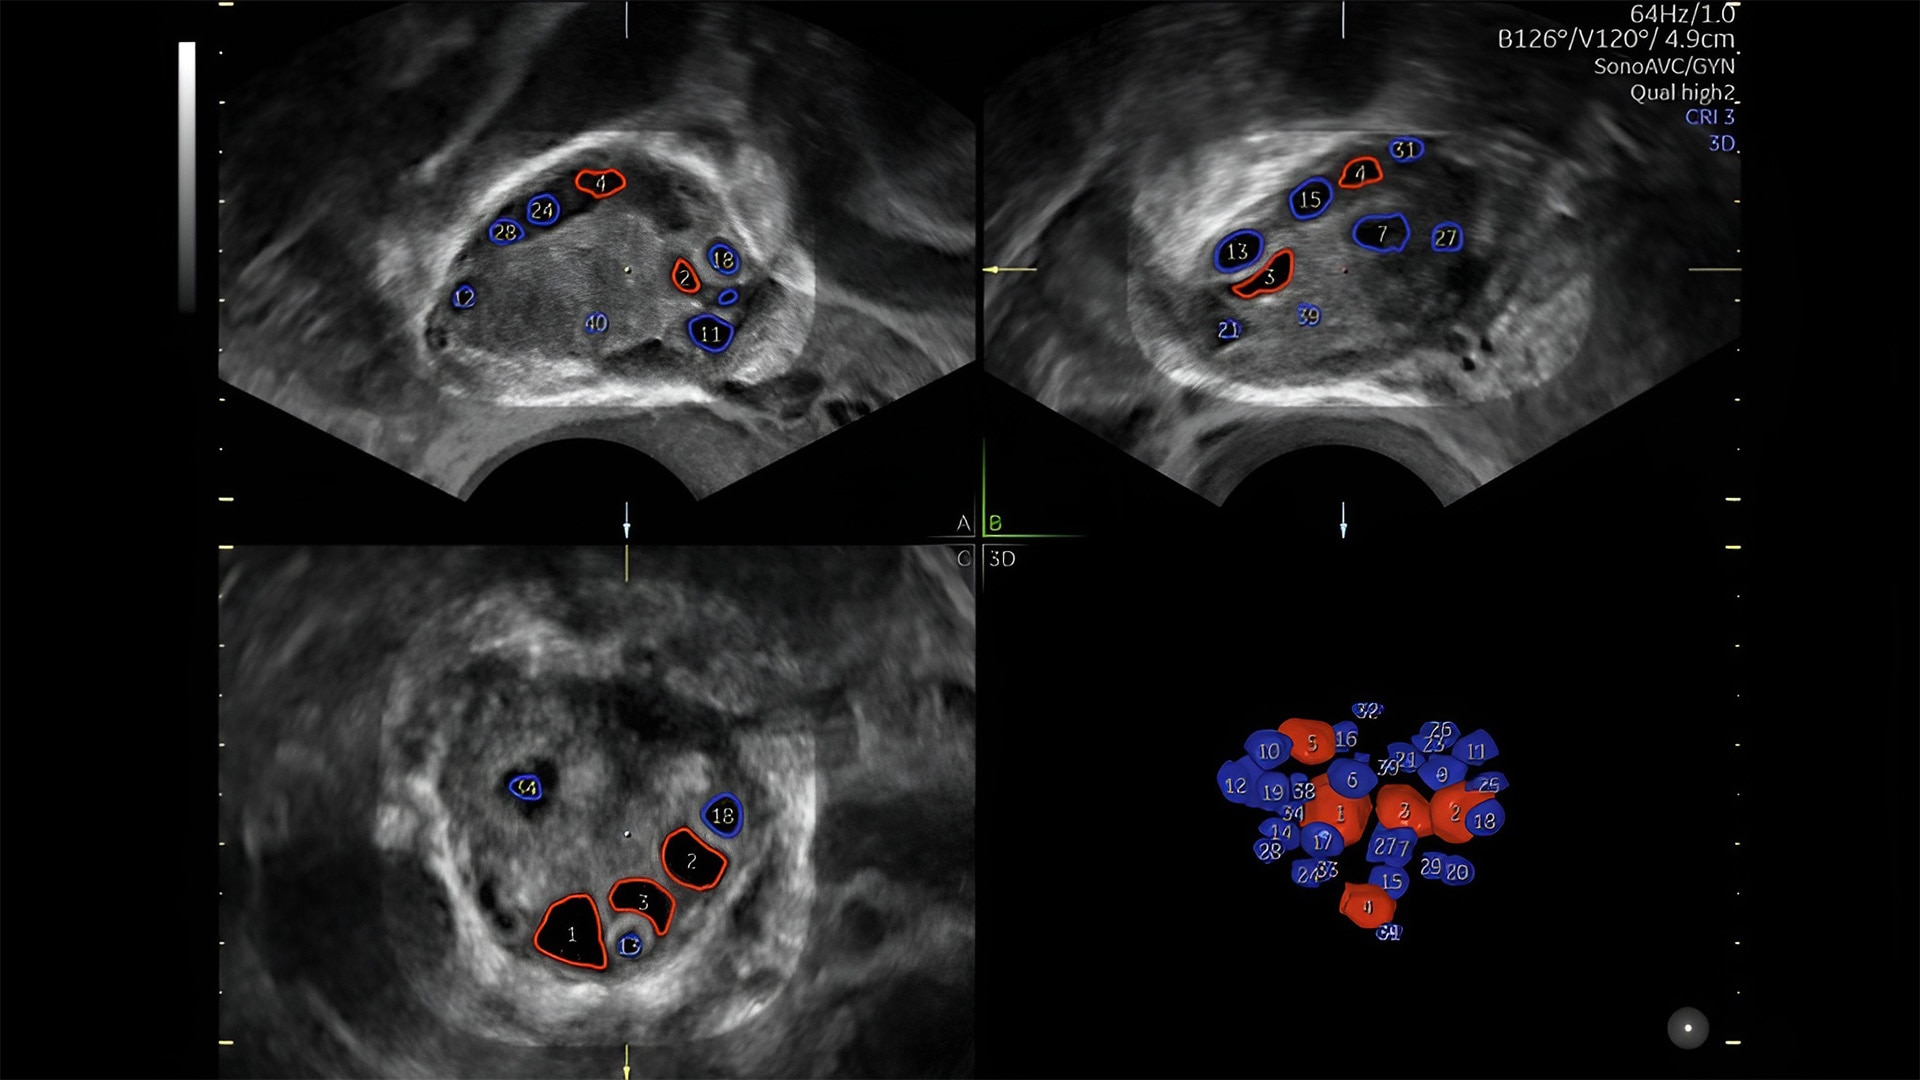

Pelvic health

Offer patient answers faster with Ai-based automation tools

Complex cases come with enough uncertainty. That's why the Voluson Expert 22 is specifically designed for in-depth assessment of complicated anatomy — with pioneering first trimester, fetal cardiac, gynecological, and other pivotal technologies that focus on early detection and intervention.

Detect the undetectable

Discover complicated anomalies and pathologies with the Voluson Expert 22 to provide answers sooner for better decision making.